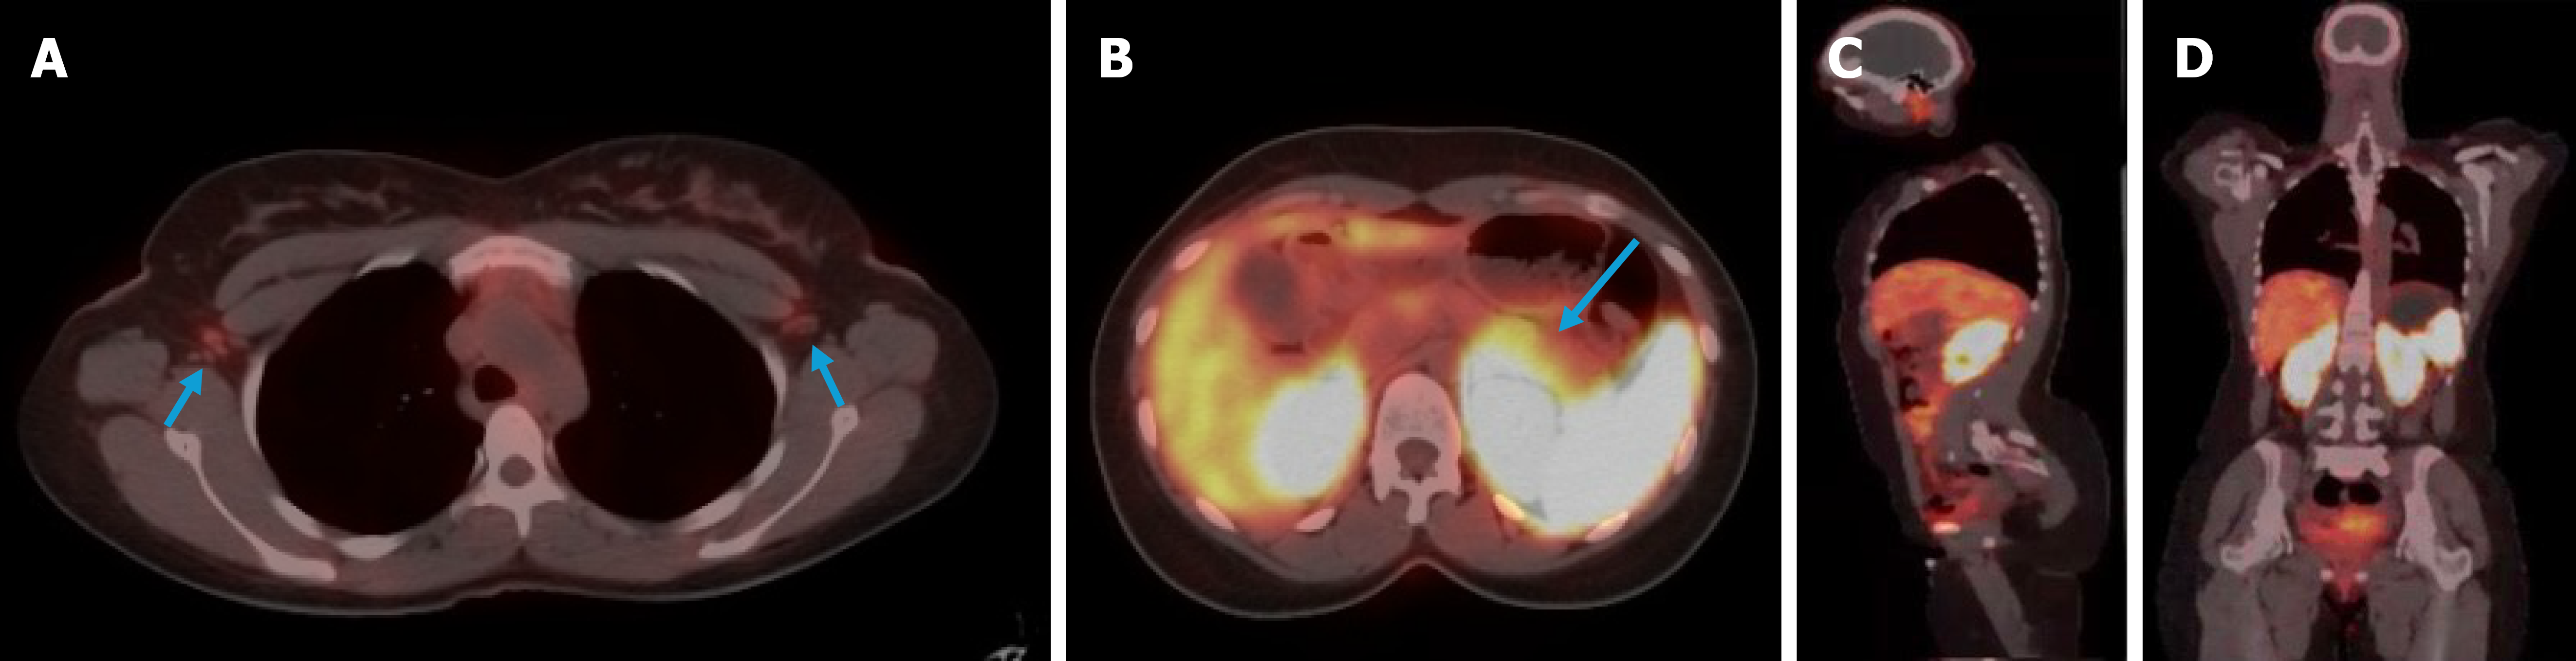

Figure 1 68Ga-DOTATOC positron emission tomography/computed tomography scans.

A: Prominent bilateral axillary lymph nodes with preserved fatty hila (reactive); B: Axial fusion: Diffuse low-grade Somatostatin receptor uptake in pancreatic body/tail (standardized uptake value max 5.1) vs head/neck (3.4); C and D: Coronal and sagittal views showing physiological tracer distribution in liver, spleen, kidneys, marrow and parotid glands.